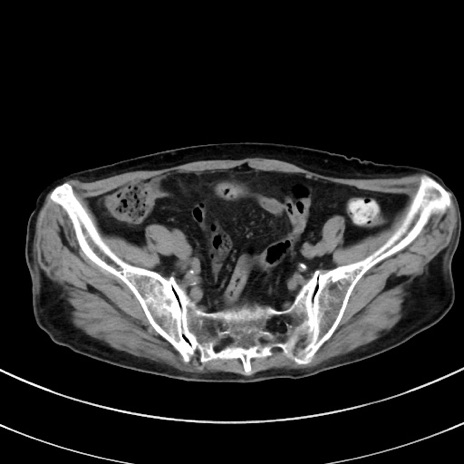

冠状断像

【症例】70歳代 女性

【主訴】心窩部痛

【現病歴】延髄病変の精査・加療にて神経内科入院中。本日より心窩部痛あり。

【既往歴】虫垂炎

【身体所見】右下腹部を中心に圧痛と反跳痛あり。

【データ】WBC 10900、CRP 0.02